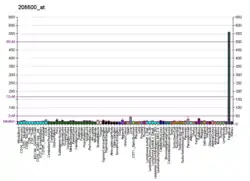

Complement component 5 is a protein that in humans is encoded by the C5 gene.[5]

Complement component 5 is the fifth component of complement, which plays an important role in inflammatory and cell killing processes. This protein is composed of alpha and beta polypeptide chains that are linked by a disulfide bridge. An activation peptide, C5a, which is an anaphylatoxin that possesses potent spasmogenic and chemotactic activity, is derived from the alpha polypeptide via cleavage with a C5-convertase. The C5b macromolecular cleavage product can form a complex with the C6 complement component, and this complex is the basis for formation of the membrane attack complex, which includes additional complement components.[5]